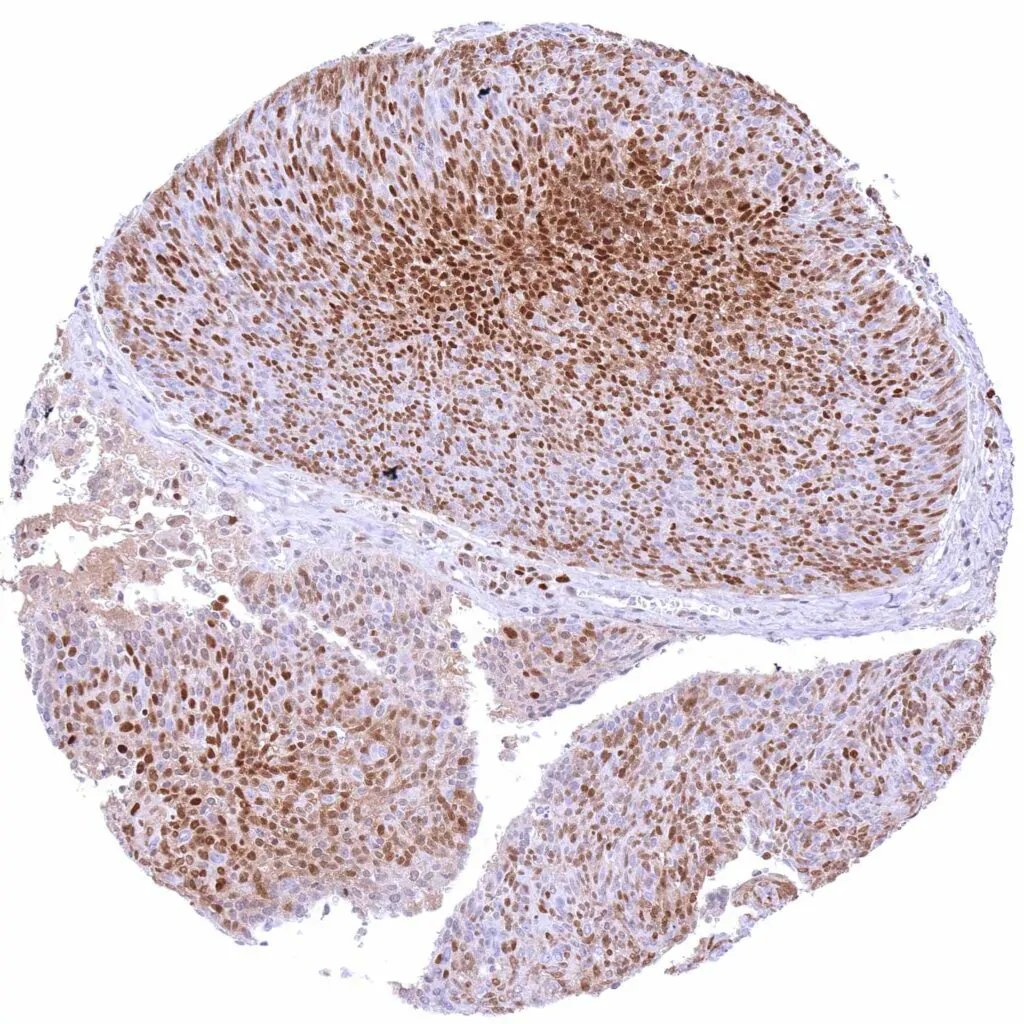

Urinary bladder – Muscle-invasive urothelial carcinoma with moderate to strong, predominantly nuclear p27 staining of tumor cells.